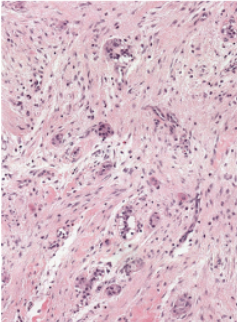

Describe the Follicular Pattern of an Ameloblastoma (3)

1) Columnar Ameloblast Like Cells at the Periphery

2) Stellate Reticulum-Like area in the Centre

3) The Epithelium resembles the enamel organ, cysts form in the Stellate Reticulum like Areas.

Describe the Plexiform Pattern of an Ameloblastoma (3)

1) Columnar Ameloblasts - like cells forming Cords

2) Little or No Stellate Reticulum like areas

3) Cysts form in the Stroma